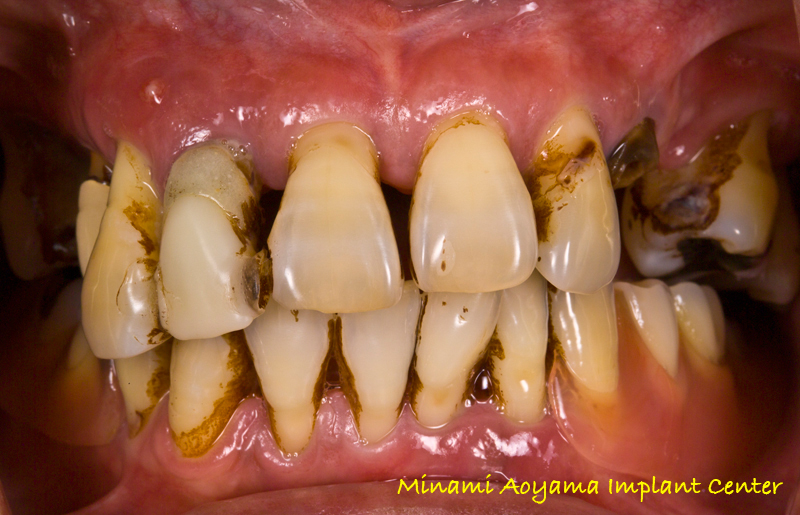

術前の状態。重度の歯周病のため歯がグラグラでほとんど何も噛むことができず

見た目にも決してきれいとは言えない状態です。

上顎が重度の歯周病であり、特に前歯がグラグラで排膿や出血がひどく、日常生活に

支障をきたしているとのこと。オールオンフォーの噂を聞き当院へご来院されました。

(従来の治療法では大幅な骨造成も必要であり、時間のかかる困難な症例です)